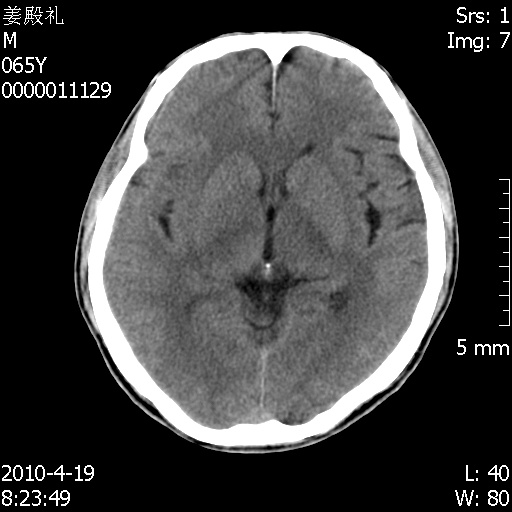

老年男性,突发左下肢无力1天,其余有价值的检查都没有。平扫ct值大约60hu,增强后ct值没什么改变,请大家讨论一下这个病例是什么?说明诊断理由。

左小脑、右大脑顶叶多发圆形高密度病灶,其周环状低密度影。考虑多发脑出血。隔期观察。

至于是出血还是微小钙化所致的高密度无法考证,三个都出血也不是一点都不可能,同一种组织学类型的肿瘤受到同一个外来的因素影响后会表现出相同的病理变化。说实在的,我本身支持转移瘤的,就是想不通为什么不强化?我认为单纯脑出血的边缘不会那么光滑,并且那也不是出血的常见部位,多发也不常见。

刚刚复习了转移瘤的不典型ct征象,有4条,分享给大家:

1、高密度灶:多为瘤内有较多沙粒体钙化所致,而不是出血,ct值可高达95hu;

2、无强化;

3、无水肿;

4、无占位效应。